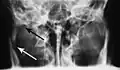

-

Towne's view of a bilateral condyle fracture. White arrow is a fracture on the neck of the condyle. Black arrow shows the condyle pulled to the medial. The same injury can be seen on the opposite side -